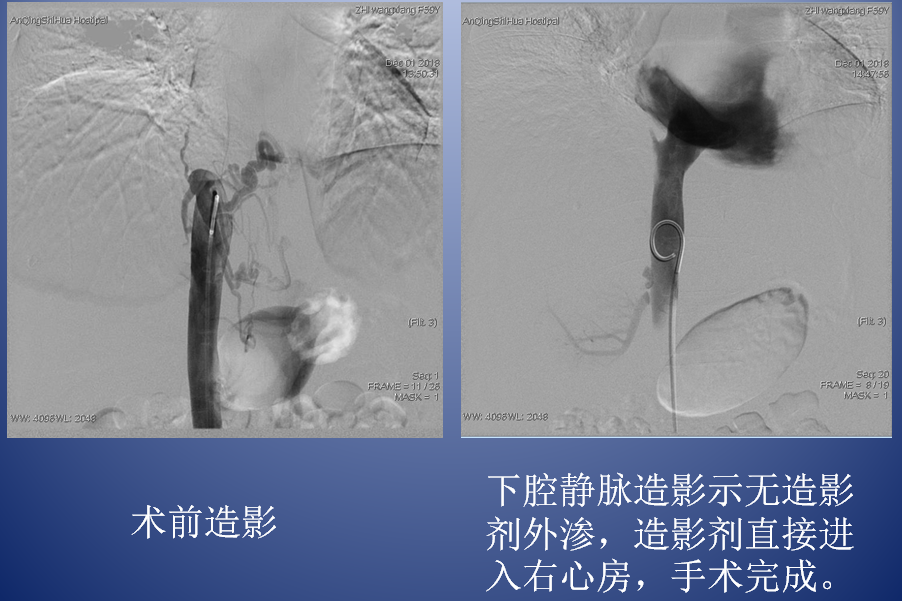

介入治療創(chuàng)傷小、效果好、并發(fā)癥少,是布加氏綜合征的首選治療方式。放射介入科團(tuán)隊(duì)認(rèn)真分析病因,反復(fù)討論病情,最終為芷女士確定了縝密的手術(shù)治療方案。12月1日,團(tuán)隊(duì)放棄周末休息時(shí)間,在外院專家指導(dǎo)下,順利為芷女士實(shí)施了腔靜脈開(kāi)通+球囊擴(kuò)張術(shù)。術(shù)后,芷女士的下腔靜脈血流立刻恢復(fù)通暢,腹圍漸漸縮小,下肢水腫明顯消退,日前,已康復(fù)出院。